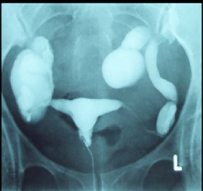

Imagem de Hidrossalpinge

HSG mostrando hidrossalpinge bilateral: as tubas estão dilatadas e o contraste fica retido, sem espalhar para a cavidade.

• Obstrução Tubária: O contraste para em um segmento, sem espalhamento. Se for distal, pode formar uma Hidrossalpinge (tuba dilatada e tortuosa).